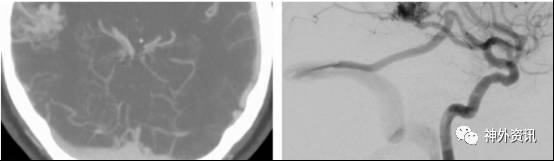

图5. 右侧颞顶叶外侧面大型、复杂AVMs(侧位和前后位的ICA脑血管造影-上图)。MCA的供血分支(左下图)和P2来源的供血动脉夹闭后切断。临时阻断静脉(右下图)以明确病灶没有血供,之后进行AVMs的离断移除。